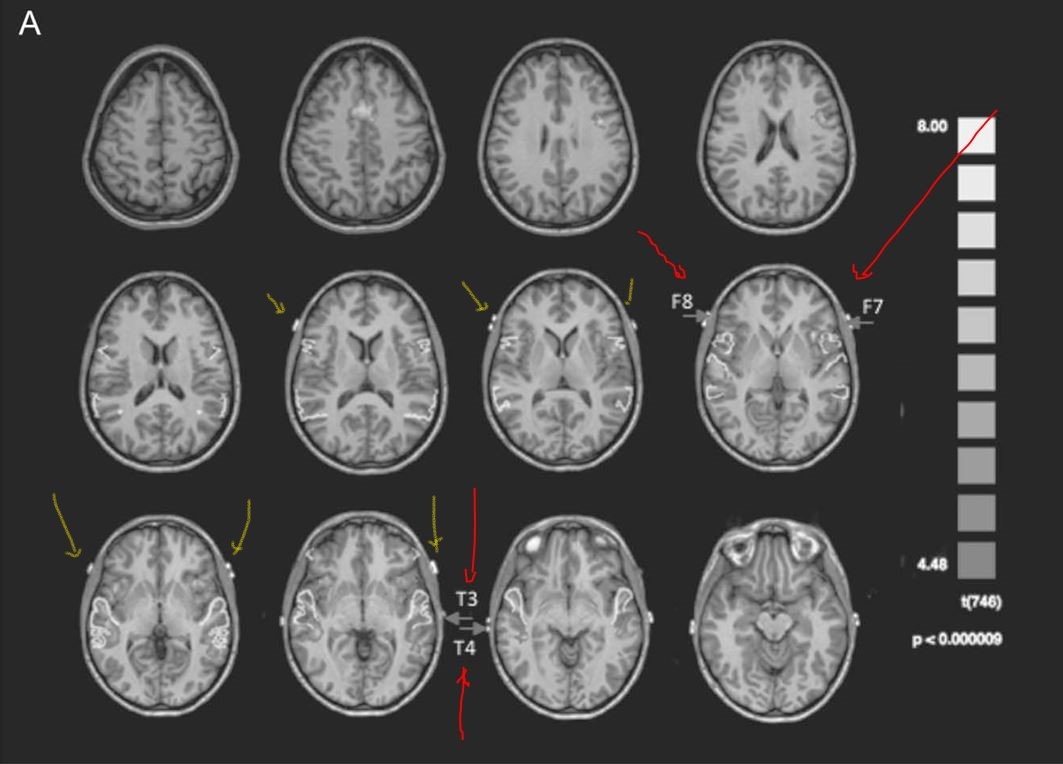

The average placement for the group is shown below. Note the variable location of F8 and F7, designated by the yellow arrows.

As you know, interictal epileptiform discharges and seizures most commonly originate within the medial temporal region. Unfortunately, F8/F7 and T4/T3 electrodes are not located over the left inferior temporal region! The average location of F8 and F7 is further forward and higher up than you might imagine; they provide more electrophysiological data from the left lateral frontal region than from the left temporal pole, which in turn is at some distance from the medial temporal lobe.

The above images demonstrate that T3 and T4 overlie the mid-temporal region in the anterior-posterior plane and most commonly lie over the middle temporal gyrus, and sometimes even over the left superior temporal gyrus. These electrodes do not face the inferior temporal region.